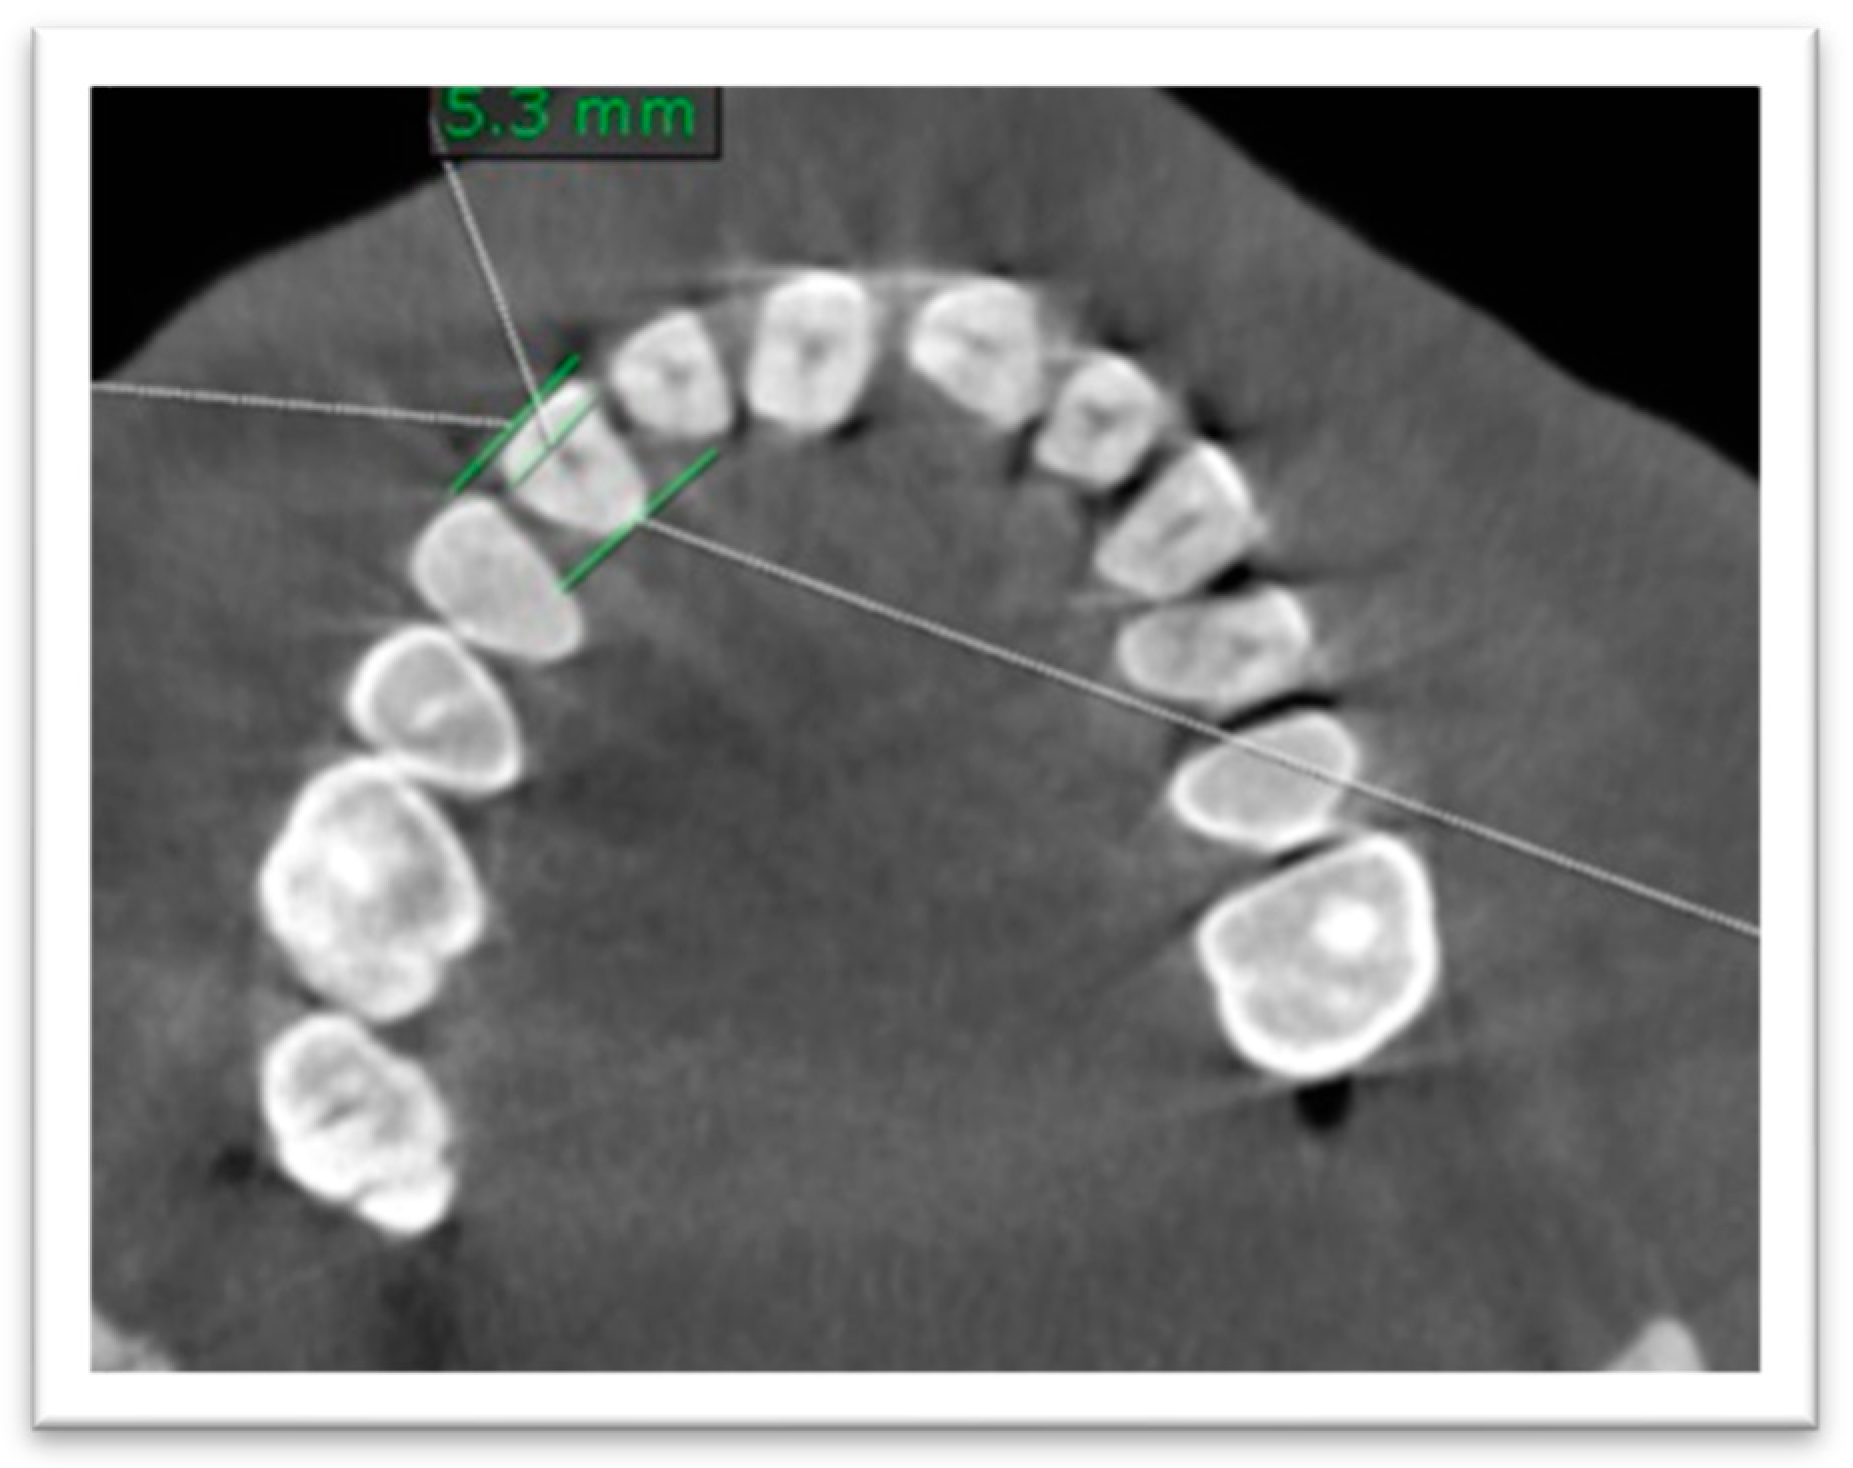

- Regarding buccopalatal diameter, it was measured at the level of CEJ by a line bisecting the tooth on the axial plane (Figure 2).